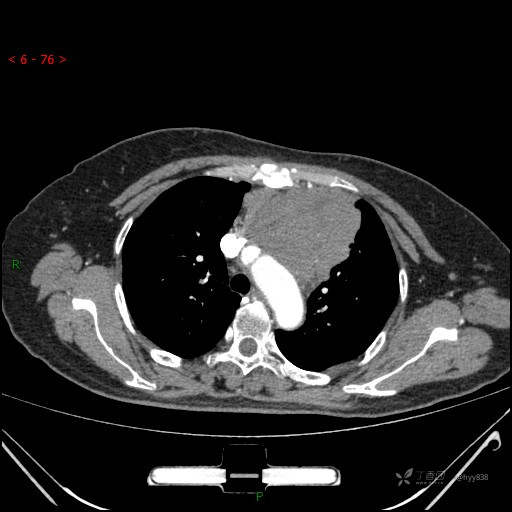

简要病史:患者诉3月余前患新冠肺炎,出现持续性胸闷,活动后可缓解,无胸前区压榨感,无畏寒发热不适,无胸痛咯血、呼吸困难,无恶心、呕吐,无腹痛、腹胀、腹泻等不适,未予以重视,未行特殊处理。患者胸闷持续存在,为进一步诊治,3天前于本院查胸部CT提示前纵膈团块状软组织密度影,肿瘤性病变可能,心包积液,左上肺磨玻璃结节,右下肺增殖灶可能建议进一步检查。门诊以“前纵膈占位” 收入我科。 患者本次起病来精神、食欲、睡眠尚可,大小便正常,体力、体重无明显变化。

辅助检查:CT

胸部CT平扫

动脉期